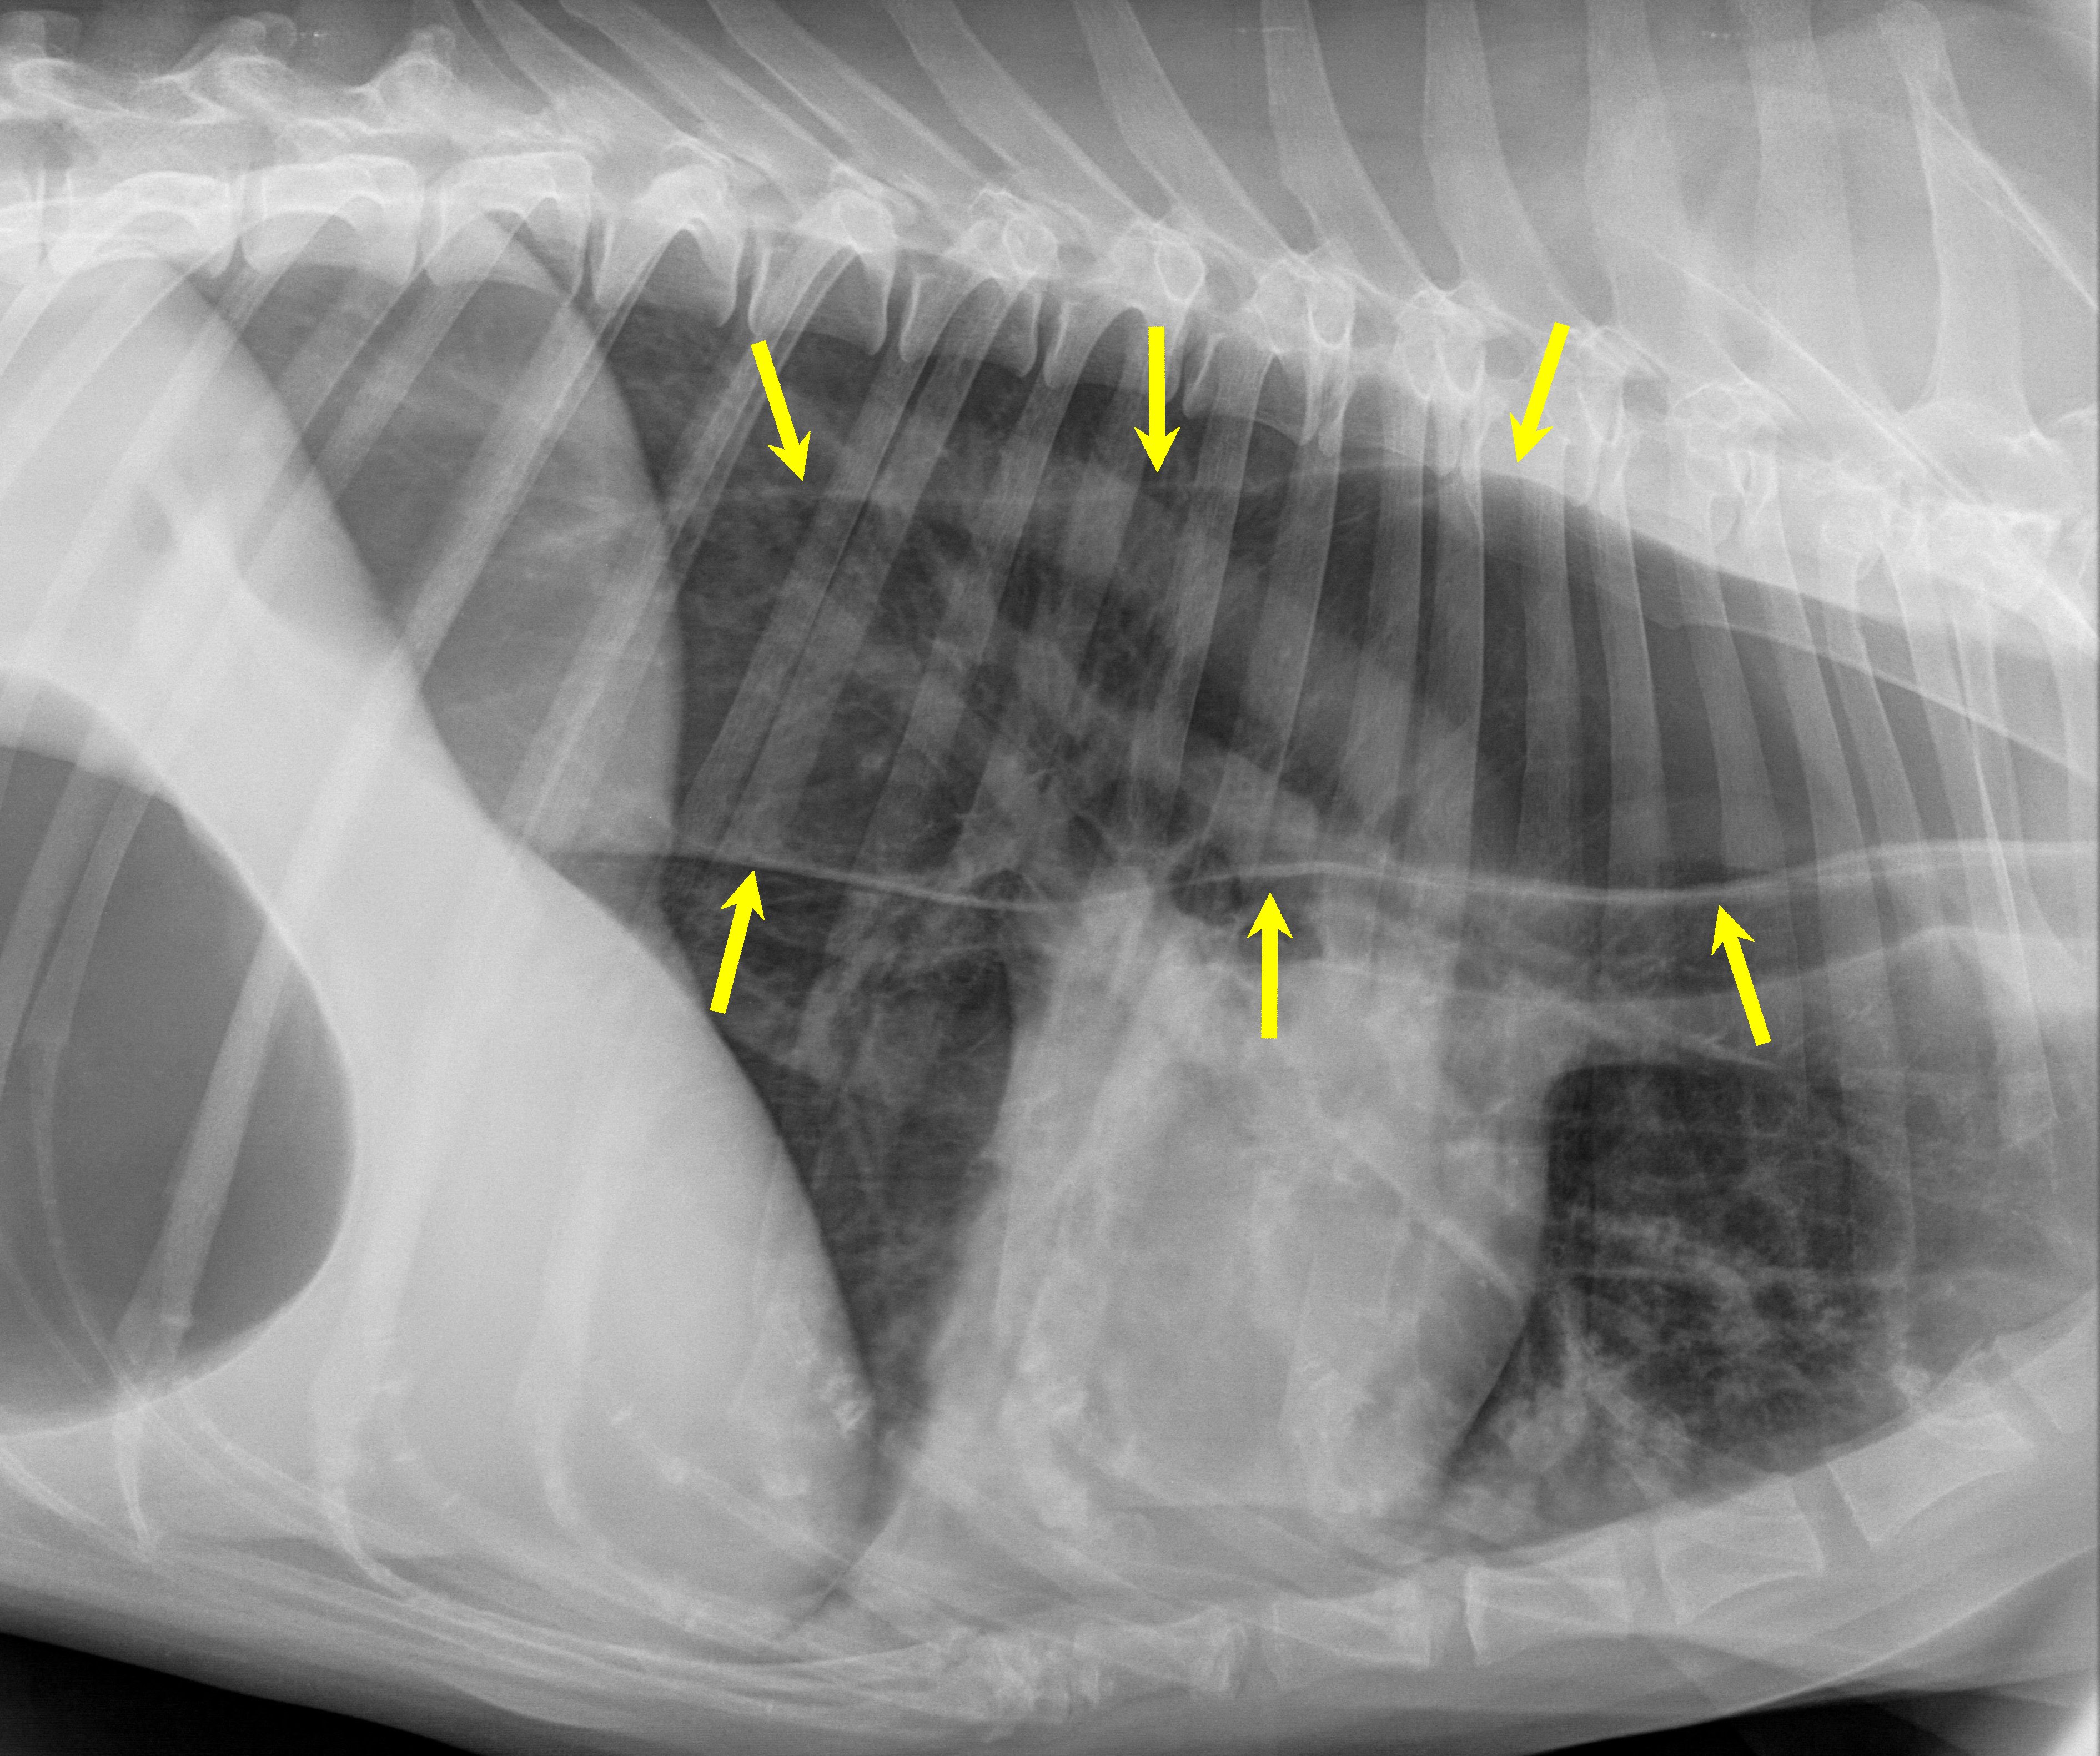

거대식도증은 식도가 비정상적으로 확장되어 음식물을 위장으로 운반하는 데 어려움을 겪는 질환이다. 사람의 경우 무이완증이나 샤가스병 등의 질병으로 인해 발생할 수 있으며, 개에게는 중증 근무력증의 증상으로 나타나기도 한다. 개, 고양이, 말 등 다양한 동물에게서 발생하며, 특히 개에서는 특정 품종에서 더 흔하게 나타난다. 증상으로는 삼킴 곤란, 역류, 흡인성 폐렴 등이 있으며, 치료 및 관리를 위해 베일리 의자와 같은 장치를 사용하기도 한다.